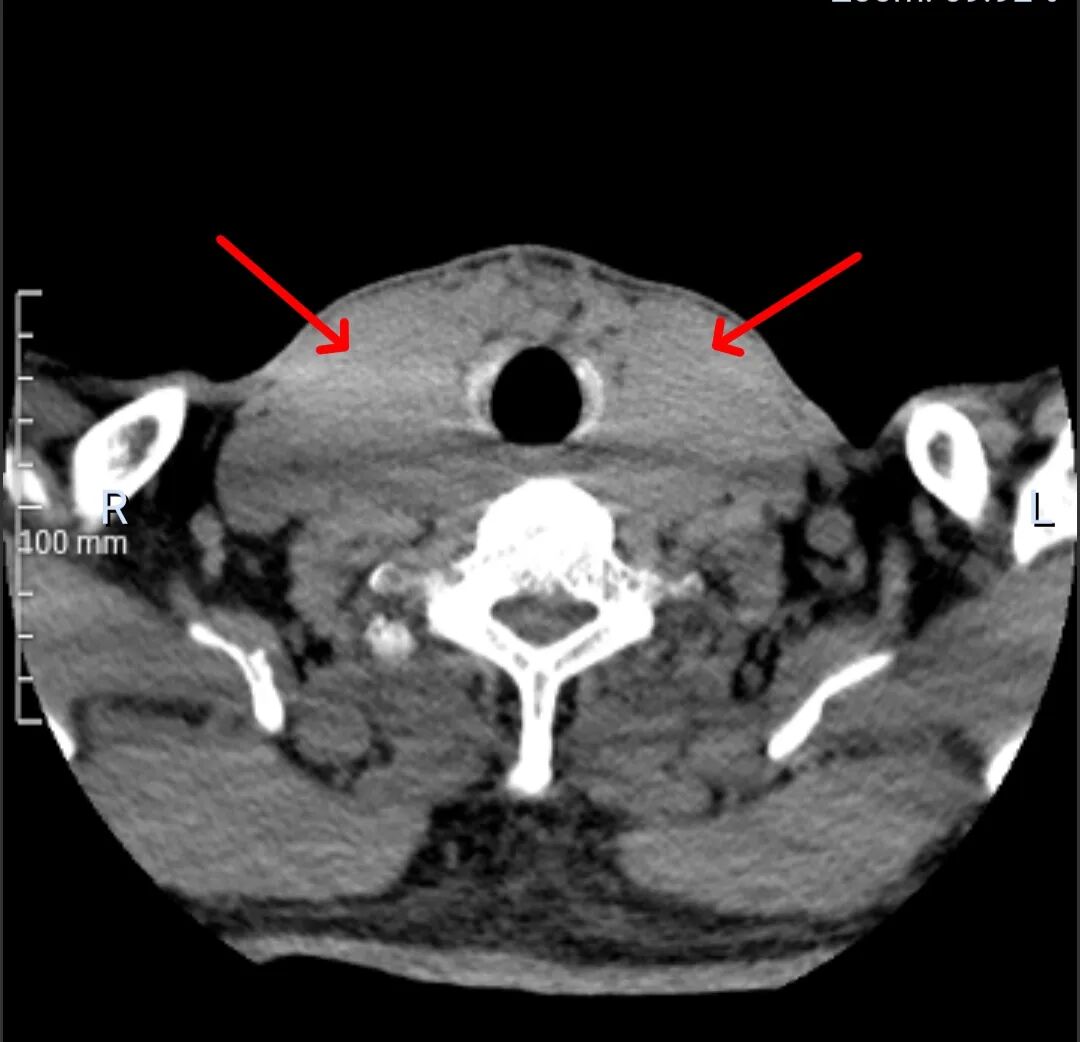

术前CT检查结果令人震惊:患者一侧甲状腺肿瘤直径已达9cm,另一侧更是巨大,直径10cm!如此巨大的肿瘤,手术难度和风险呈几何级数攀升。这无疑是一枚埋在颈部的“定时炸弹”,时刻威胁着患者的生命安全。